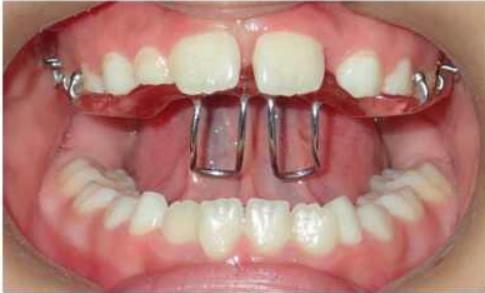

1. 前牙反合

前牙反合,俗称“地包天”,是指上下颌牙齿咬合时,下颌前牙咬在上颌前牙的外面。前牙反合随着患者的生长,症状会逐渐加重,往往造成上颌骨发育不足、下颌骨发育过度,表现为凹面型,对患者的美观、功能及心理健康均带来了极大的不良影响。乳牙列时期的前牙反合一般在3-5岁左右进行。混合牙列的前牙反合一般在8-9岁左右。

矫治方法:前牙反合的患儿往往伴有咬上唇、伸下巴、口呼吸等不良习惯。因此,应首先纠正其不良习惯。口呼吸习惯应进行耳鼻喉科会诊处理,检查其是否伴有鼻咽部疾病,排除鼻咽部疾病后,再进行纠正。对于乳牙列,常用的矫治器为合垫舌簧矫治器;对于混合牙列,常用的矫治器为前方牵引矫治器和FRⅢ矫治器。

① 合垫舌簧矫治器

② 前方牵引矫治器

③ Frankel Ⅲ矫治器